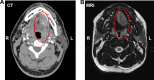

Case presentation: A 33-year-old Chinese man presented with a progressively enlarging mass at the base of his left tongue. Contrast-enhanced computed tomography and magnetic resonance imaging revealed an augmented soft tissue mass in the left jaw region with indistinct boundaries, enlargement of cervical lymph node of uncertain etiology, and no evidence of distant metastasis. A transoral needle biopsy from the mass pathologically revealed low-grade mucoepidermoid carcinoma. Complete transoral excision and cervical lymph node dissection were performed, followed by reconstruction with an anterolateral thigh free flap. Examination of the obtained surgical specimen confirmed low-grade mucoepidermoid carcinoma with MAML2 gene fusion in the base of the tongue. The tumor was removed with negative margins, and the cervical lymph nodes were free of disease. The patient had an uneventful recovery and showed no evidence of recurrence or metastasis at 40 months of follow-up.